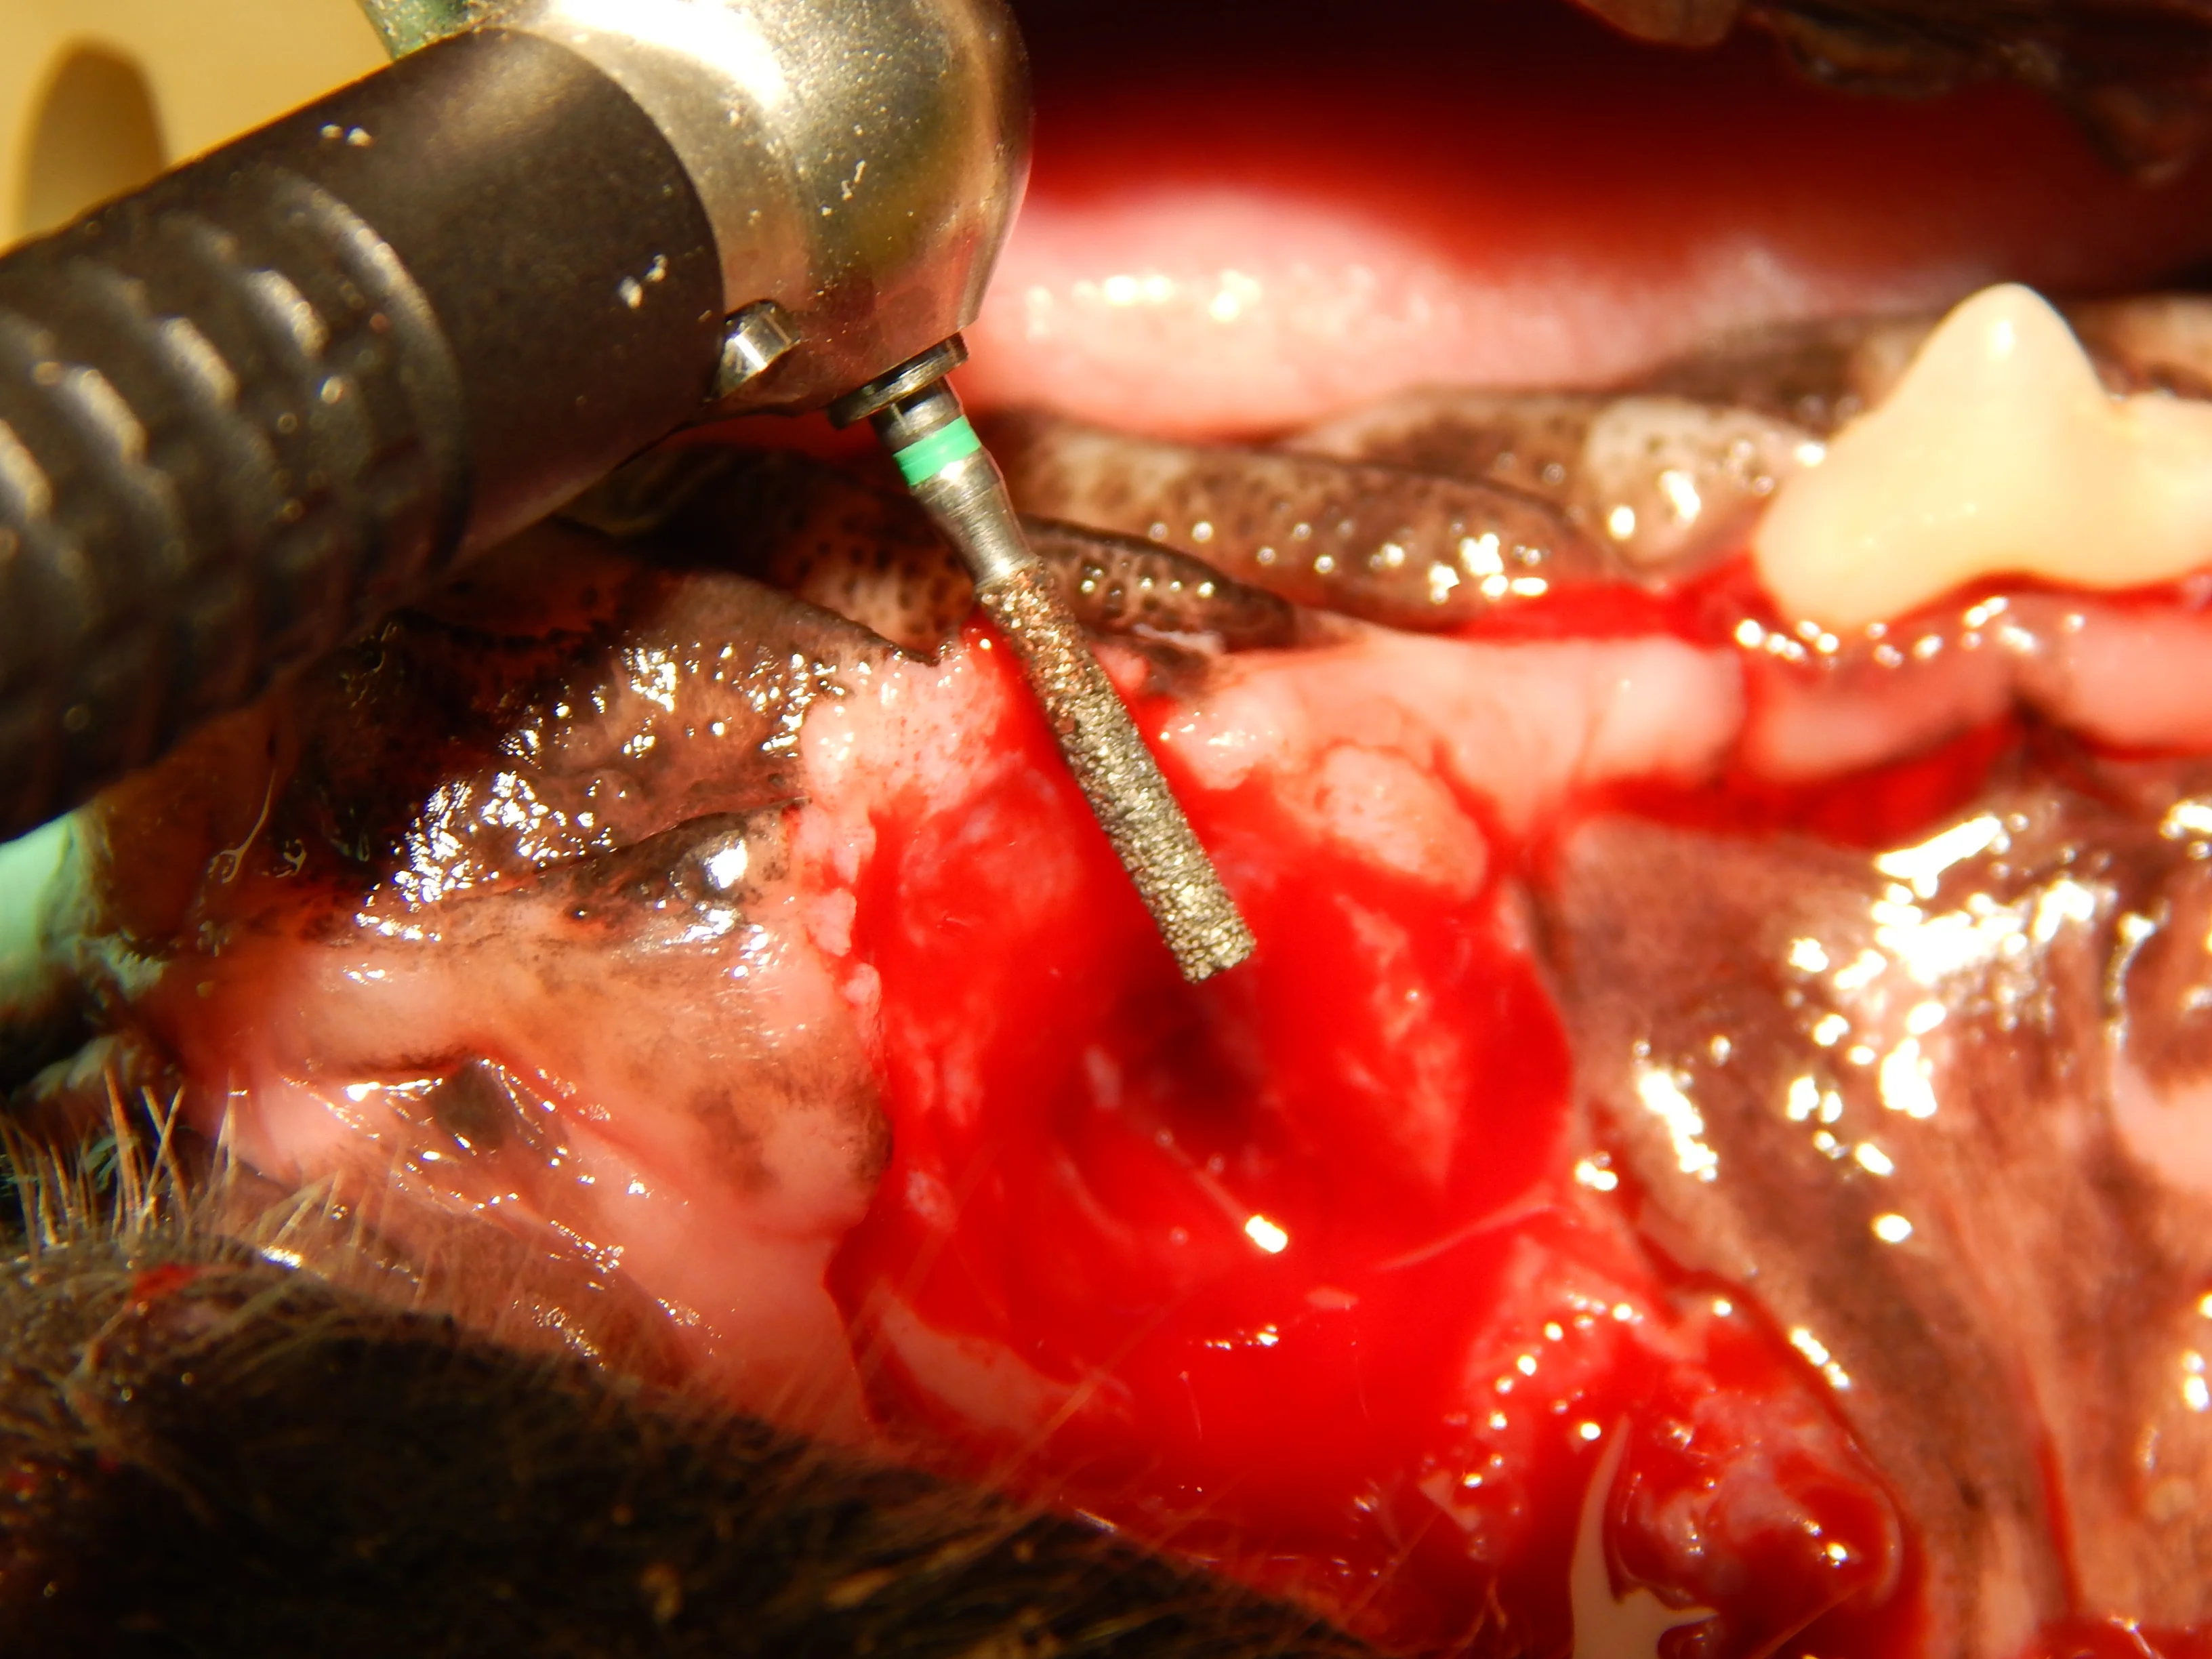

Oronasal fistulas may often be present prior to surgical extraction of maxillary teeth (Figures 6 and 7) but can also be a result of the surgical procedure. Although any maxillary tooth extraction can result in an oronasal fistula, it is most common following extraction of a maxillary canine tooth. Inadequate healing may lead to chronic oronasal fistulation (Figure 8). The quality of the tissue used to close the fistula and lack of wound tension are especially important in closure of oronasal fistulas. Development of a healthy recipient bed for the flap (Figure 9) and use of an Elizabethan collar to prevent self-trauma by the patient can also reduce flap failure.4

A coarse cylindrical diamond bur used to create a recipient bed (A). Removal of the epithelium allows improved healing of the sutured mucogingival flap (B).